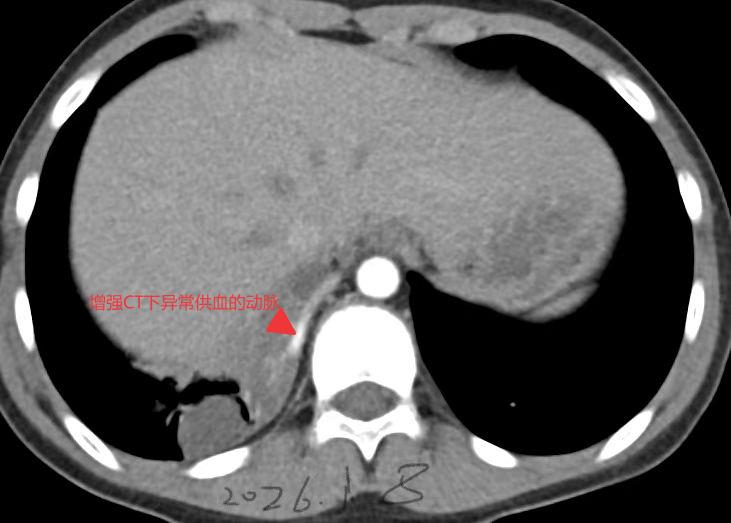

2026.01 胸部增强CT提示异常供血的动脉

肺隔离症的诊断需要结合影像学检查和血管评估,单纯依靠症状难以确诊。目前主要依靠胸部增强CT来确诊,能够清晰地显示异常供血动脉(多来自胸主动脉或腹主动脉)和引流静脉;明确异常供血动脉的存在是确诊肺隔离症的核心依据。单纯肺内病变而无异常血管,不能诊断为肺隔离症。